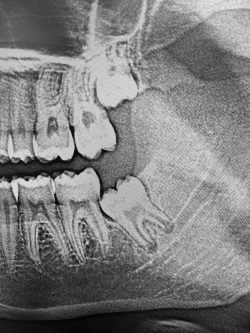

Cases shown are 1) upper and lower arches of bombed-out teeth (included one socket graft using a PGA membrane), 2) erupted thirds, 3) impacted 3rds in a young person.  The PGA membrane is done like a PTFE membrane but does not need to be removed.

This was a “surgical extraction” course but unpredictably had some 3rd molars in the mix.